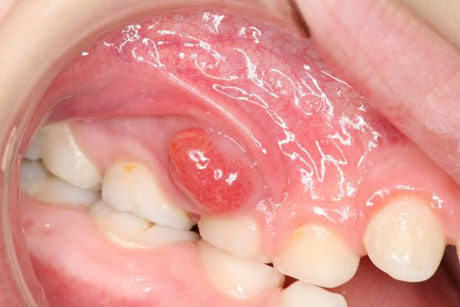

Peri-coronal Abscess: This kind of usually forms around an impacted tooth i.e. one that has not fully grown into the mouth or is partially covered by part of the gum. Most commonly affected teeth are wisdom teeth. This infection should be treated immediately because of the risk of spread to the neck area and down into the chest causing blockage to the airway (Ludwig’s Angina). This is a life-threatening hospital emergency. Treatment of the peri-coronal abscess involves antibiotic therapy and extraction of the offending tooth.